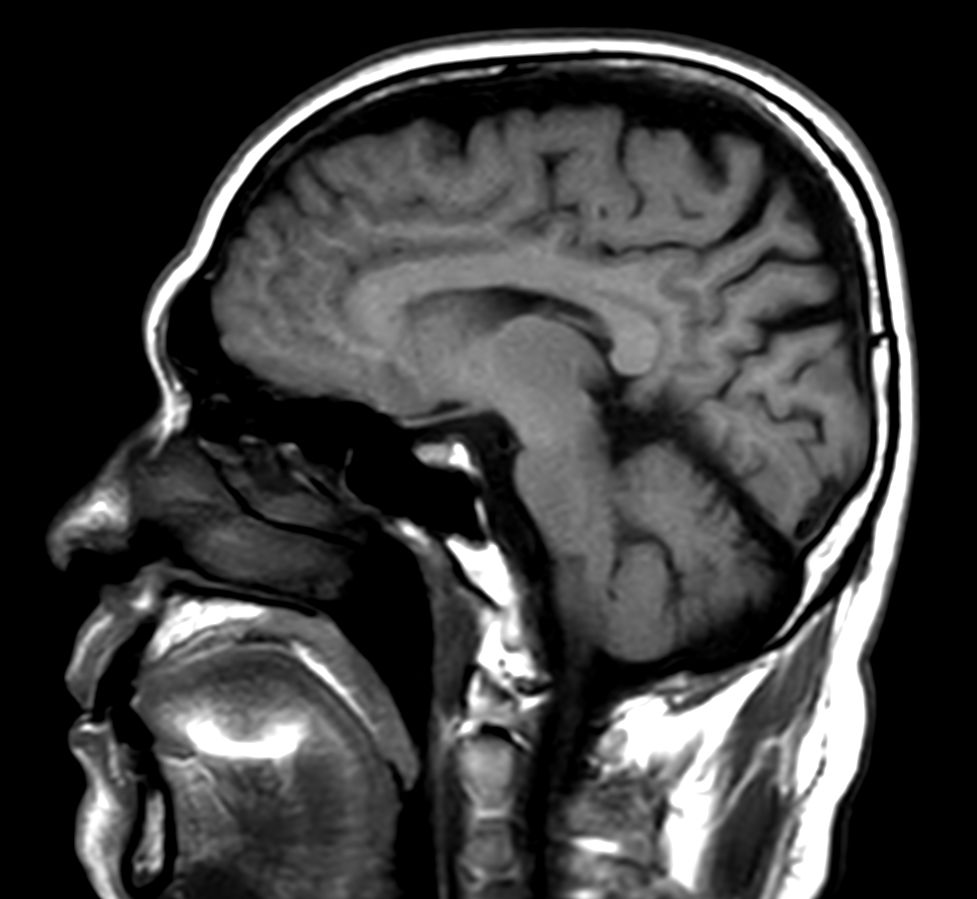

Brain infarction

Patient with a brain infarction. Compressed SENSE is used to shorten the total exam time.

T1w SE - Compressed SENSE